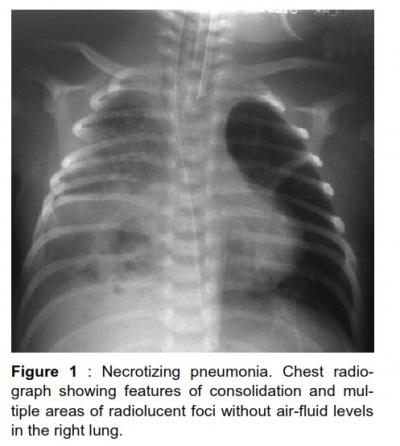

Coagulase negative staphylococcus necrotizing pneumonia

Article | July 20, 2012 - 11:20am | By Johan AJ, Cheah FC